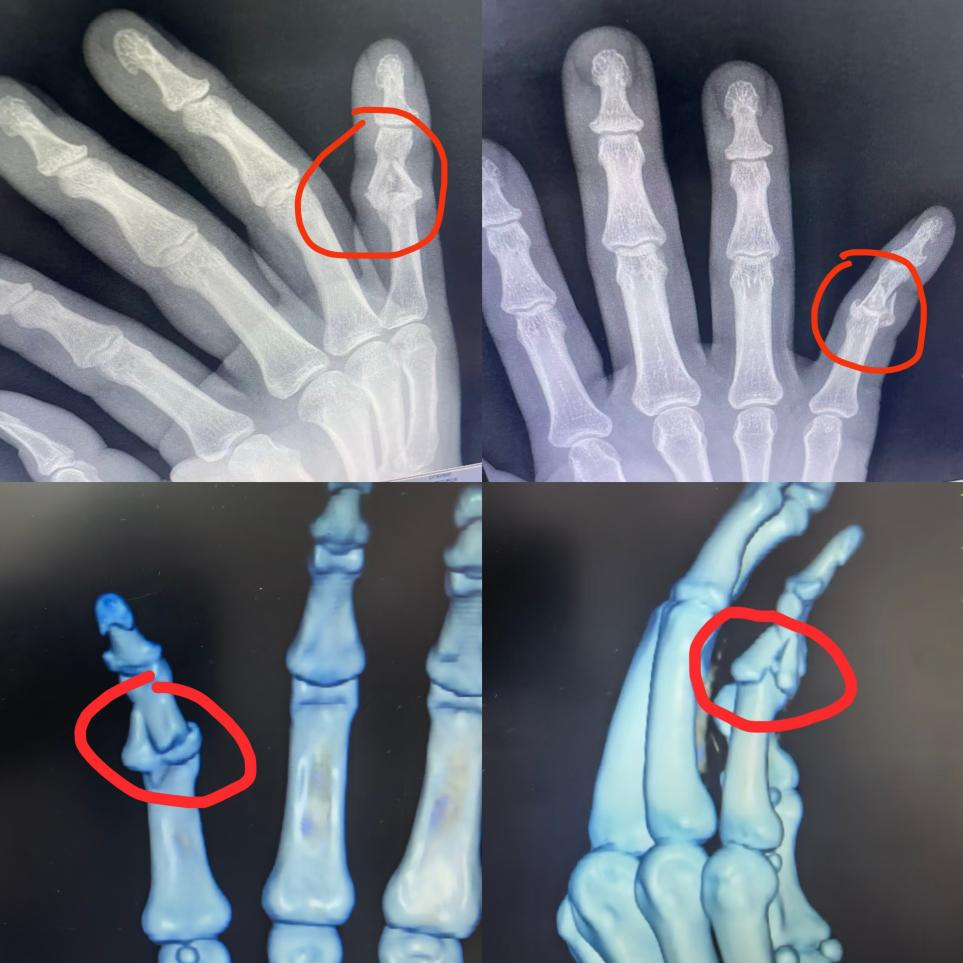

“本以为得开刀动大手术,没想到就打了两根细针,4天就出院了,现在手指恢复得特别好!”近日,36岁的吴先生(化名)在河南科技大学第一附属医院(以下简称河科大一附院)开元院区骨科(创伤外科)复查时,看着清晰的骨折愈合影像,对科室团队连连称赞。此前,他因骑车摔倒导致右小指Pilon骨折(指骨粉碎性骨折),在多家医院建议切开手术的情况下,河科大一附院开元院区骨科(创伤外科)团队通过克氏针铃木架技术实现闭合复位,避免了创伤与后遗症。

近日,吴先生骑车时不慎摔倒,右手重重着地,当即出现剧烈疼痛、活动受限。他紧急前往附近医院检查,诊断为右小指中间节指骨Pilon骨折,骨折块竟达6块,且已损伤关节面,属于复杂难治性骨折。

接诊后,石辉辉仔细研究了吴先生的影像学资料,发现其骨折情况比预想更复杂:6块碎骨如同散架的积木,常规钢针固定易导致骨头进一步碎裂,钢板螺丝更是无处可拧。为制定万无一失的方案,石辉辉第一时间将情况向科室主任熊明月、副主任李向明进行了汇报。

“不能让患者白受开刀之苦!”熊明月带领团队反复研讨,最终决定采用克氏针铃木架技术,这项技术专为指骨Pilon骨折设计,核心优势在于“闭合复位牵开关节”,无需切开皮肤,就能实现精准复位与功能保护。“简单说就是在手指上下端各穿一根细克氏针,搭建微型外牵引架,用皮筋牵引悬吊,利用牵引力让碎骨自动对齐归位,同时牵开关节面,避免粘连。”石辉辉解释,该技术还能支持早期活动,进一步改善关节功能,从而降低后遗症风险。

术后一周复查时,影像学检查显示,6块碎骨已精准复位,骨折线清晰可见,关节面平整无损伤。“没想到不用开刀,碎骨头还能复位得这么好!”看到复查结果,吴先生惊喜不已。